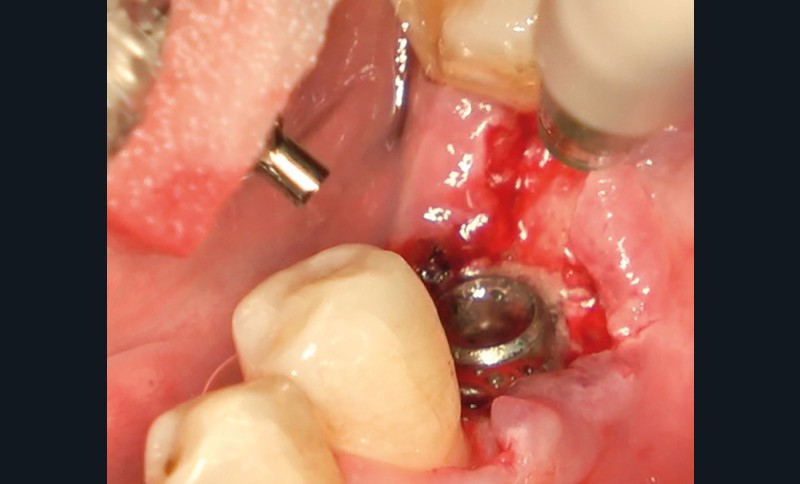

- Un implant posé en 2018 après la fin du traitement orthodontique

- Péri-implantite diagnostiquée en 2021

Chez ce patient, le traitement de la péri-implantite a comporté une chirurgie associant décontamination électrolytique de la surface implantaire, régénération osseuse guidée et enfouissement de l’implant. Le résultat à 2 ans est très moyen au vu du pourcentage de régénération osseuse obtenu. Comment peut-on prévoir un tel résultat alors que l’on a suivi les recommandations à la lettre, que l’on a utilisé les dernières technologies de décontamination, que l’on y a mis tous les moyens, que le patient est en bonne santé générale et qu’il vient en plus régulièrement aux séances de thérapeutique de soutien ? Le succès du traitement des péri-implantites n’est pas simple à obtenir, surtout quand un élément clé est compromis… la maintenance personnelle ! En effet le succès n’est possible que si le contrôle de plaque quotidien est optimal et, ici, ça n’était pas le cas. Le patient se brossait certes les dents, mais ne passait pas quotidiennement les brossettes, ce qui…